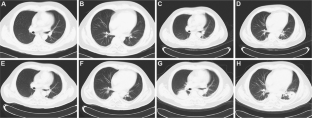

Fig. 1

Fig. 2